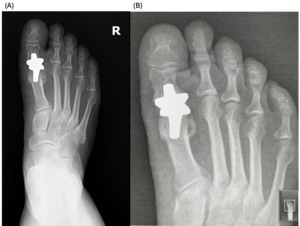

._patient_a__immediate_postoperative_radiograph_(b).png)

._patient_a__6-month_follow-up_radiograph_(b).png)